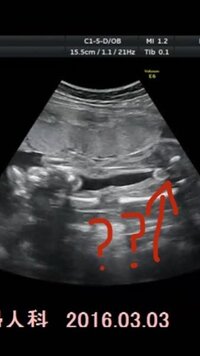

24週エコーです 性別は女の子ぽいでしょうか わかる方お願い Yahoo 知恵袋

性別判定19w3dです 女の子希望なのですが このエコー写真だと ど Yahoo 知恵袋

妊娠7ヶ月です おまたの下から撮ったエコーです 男の子か女の子か 妊娠 教えて Goo

このエコー写真は男の子か女の子か分かりますか このエコー写真は男 妊娠 教えて Goo

エコー写真性別判断相談 エコー写真性別相談お願いします 女の子 男の子 Okwave

こちらのエコーは女の子ですか 男の子ですか 妊娠7ヶ月目 24 Yahoo 知恵袋

エコー写真あります 女の子か男の子 このエコー写真からお分かりになられ Yahoo 知恵袋

エコー写真で質問です 6ヶ月の妊婦です 先月は男の子かなぁ と言われ 今月は Yahoo 知恵袋